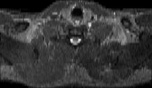

Visible Human male: Sectio transversalis 1284

CT